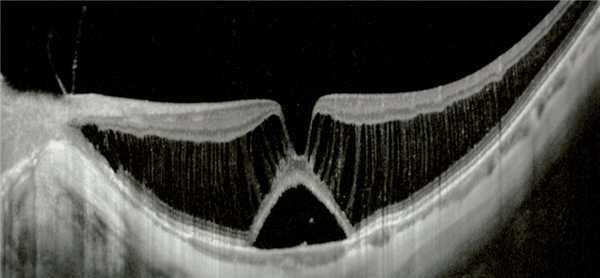

Рис.1 Картина глазного дна (А) и ОКТ (B) при Х-сцепленном ретиношизисе (стрелкой показано «гофрирование» глубоких слоёв сетчатки)

Рис.2 Картина макулошизиса (снимок ОКТ — оптической когерентной томографии)

Наиболее информативным методом исследования при этой патологии является ОКТ (оптическая когерентная томография). [5] Он дает возможность наиболее точно определять имеющиеся поражения макулярной области, выявлять кисты, а также возможные отслойки в периферийной области.